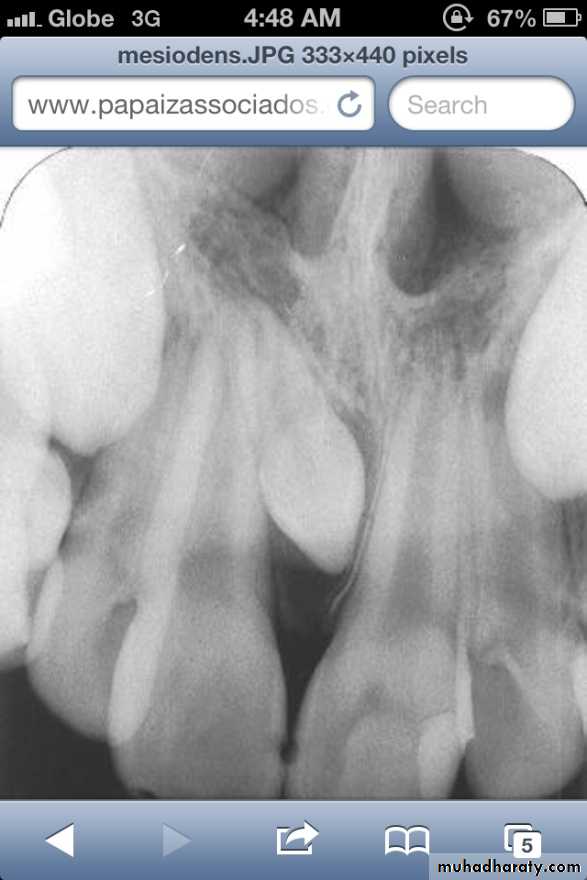

• Mesiodens :When they occur between the maxillary central incisors.

• Common region of the jaws to be affected is the premaxilla.

Mesiodens

Many supernumerary teeth never erupt, but they may delay eruption of nearby teeth or cause other dental problems.